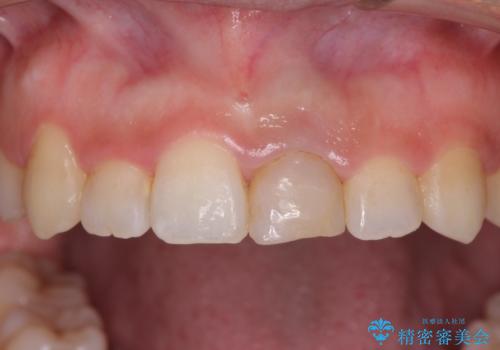

前歯のクロスバイトと変色した歯 ワイヤー矯正とセラミック治療

- 前歯のクロスバイトと神経を取り除いた後に変色してしまった前歯を気にして来院された患者様です。

ワイヤー矯正により矯正治療を行った後に、前歯の補綴治療を行うこととしました。

変色してしまった前歯は、反対側の歯と比べて歯肉が覆い被さっていたため、骨整形を含めた歯周外科処置を行い、歯肉ラインを整えることとしました。

インビザラインでの矯正治療も十分に対応可能でしたが、自己管理の煩わしさから、ワイヤー矯正を行うこととしました。

歯周外科処置を行うかどうかは非常に悩んでいらっしゃいましたが、範囲がそれほど広くないため術後の痛みも強くないだろうということで、処置を行うこととなりました。